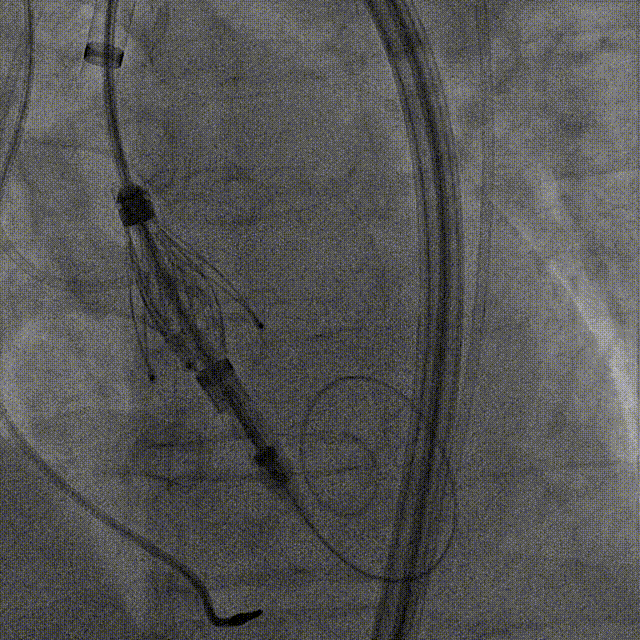

手术过程:5A 标准化流程SOP

左冠造影

小右冠,弥漫性病变

LAD术后造影

根部造影

长鞘植入

输送器定位

右窦中心对齐

定位键窦对齐

无窦确认

右窦观察

左窦确认

深度确认

一键脱钩

术后造影